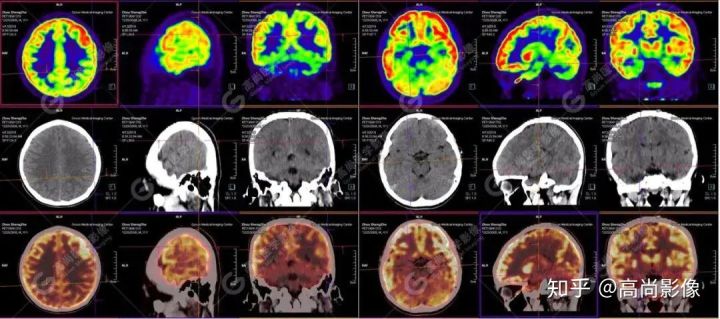

【PET/CT 】

提示: 大腦左側(cè)頂葉、顳葉(上部)及右側(cè)額葉、枕葉、顳葉(下部)腦皮質(zhì)代謝廣泛減低,尤以右枕葉為著,多考慮與癲癇發(fā)作相關(guān)。